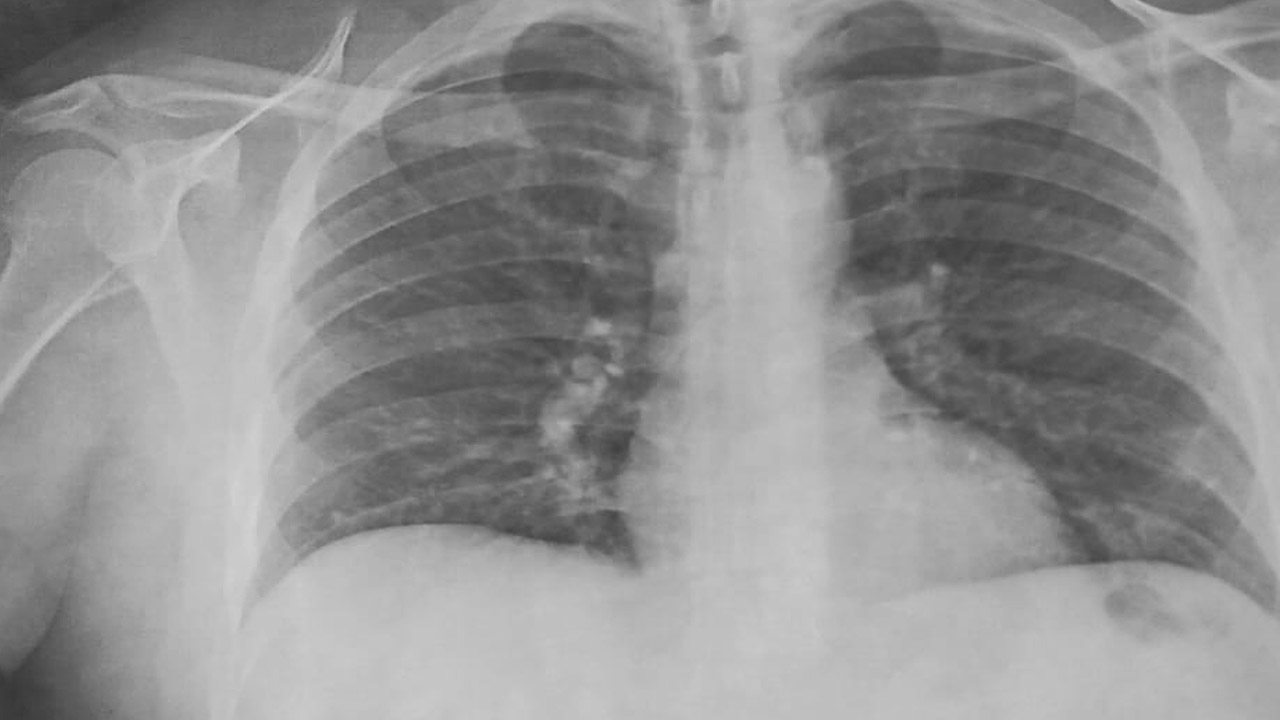

Rayos X Covid Positivo

Tromboembolismo Pulmonar Masivo Paciente Neumonia Covid 19 Positivo Revista Chilena De Anestesia

revistachilenadeanestesia.cl

La Radiologia En El Diagnostico De La Neumonia Por Sars Cov 2 Covid 19 Medicina Clinica

www.elsevier.es

Aspectos Radiologicos Del Covid 19 Cardiologia Hoy

cardiologiahoy.com